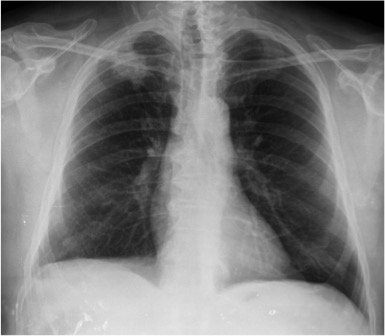

Mismo paciente, al cual esta vez se le ha tomado una radiografía en PA y en sedestación. Observar como las clavículas están equidistantes a las apófisis espinosas y como ha desaparecido el velamiento del pulmón izquierdo.

Por otra parte, paciente presenta una cardiomegalia y un discreto ensanchamiento del mediastino es probable relación con cambios postquirúrgicos.